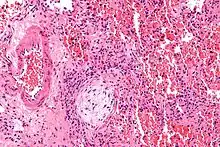

Micrograph showing a Masson body (off center left/bottom of the image – pale circular and paucicellular), as may be seen in cryptogenic organizing pneumonia. The Masson body plugs the airway. The artery associated with the obliterated airway is also seen (far left of the image). H&E stain. | |

Organizing pneumonia is usually preceded by some type of lung injury that causes a localized denudation or disruption in continuity of the epithelial basal laminae of the type 1 alveolar pneumocytes that line the alveoli.[9] This injury to the epithelial basal lamina results in inflammatory cells and plasma proteins leaking into the alveolar space and forming fibrin, resulting in an initial fibroblast driven intra-alveolar fibroproliferation.[9] The fibroblasts differentiate into myofibroblasts and continue to form fibrosis resulting in intra-alveolar fibroinflammatory buds (Masson's Bodies) that are characteristic of organizing pneumonia.[9] These Masson's bodies consist of inflammatory cells contained in an extracellular matrix consisting of type I collagen, fibronectin, procollagen type III, tenascin C and proteoglycans.[9] Angiogenesis , or the formation of blood vessels, occurs in the Masson's bodies and this is driven by vascular endothelial growth factor.[9] Remodeling occurs, resulting in the intra-alveolar fibroinflammatory buds (Masson's Bodies) moving into the interstitial space and forming collagen globules that are then covered by type 1 alveolar epithelial cells with well developed basement membranes. These type 1 alveolar epithelial cells (pneumocytes) then proliferate, restoring the continuity and function of the alveolar unit.[9] This process is in contrast to the histopathologic changes seen in usual interstitial pneumonia where extensive fibrosis and inflammation occur leading to fibroblastic foci to form in the alveolar spaces resulting in obliteration of the alveolar space, scarring and significant damage to lung architecture (the alveoli).[9]

Biopsy findings in patients with organizing pneumonia consist of loose connective tissue plugs involving the alveoli, alveolar ducts and bronchioles. The loose connective tissue plugs occupying the alveolar spaces often connect to other connective tissue plugs in nearby alveoli via the pores of Kohn creating a characteristic butterfly pattern on histology.[9] There is usually minimal to no interstitial inflammatory changes in biopsies of organizing pneumonia.[9]

Histologically, cryptogenic organizing pneumonia is characterized by the presence of polypoid plugs of loose organizing connective tissue (Masson bodies) within alveolar ducts, alveoli, and bronchioles.